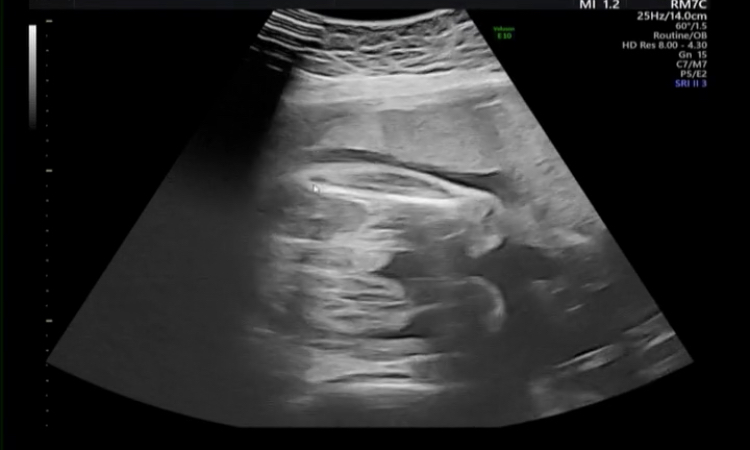

またもやご質問申し訳ないのですが、先生はこのエコー写真を見て、男児の外性器がしっかりついていると思われますでしょうか?。>_<。

赤ちゃんのエコー写真についてですね。

ついているようにも見えますが、断定はできません。

実は先日、尿道下裂の可能性があるかも。と医師から言われました。 妊娠初期から見ていただいていた産院から、今は里帰り先の産院での検診になっているのですが、 元々見ていただいていた産院ではずっと男の子だね。と言われていました。エコーの写真も何枚かあります。 今、妊娠35週になるのですが、この時期に尿道下裂の指摘をされることはあるのでしょうか?😢 教えていただけると嬉しいです。

今の産院の先生に、前の産院でもらった外性器のエコー写真を見せた所、ちゃんとついているね。もしかしたら、僕の見間違いかもしれない。と言われもしたのですが、20週前後に確実に見られた外性器が35週では見えにくいって事は考えられるのでしょうか?。>_<。